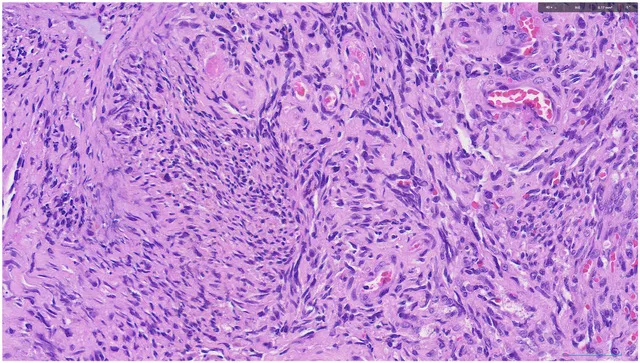

Imágenes:

2 H&E

Diagnóstico: SARCOMA DE KAPOSI, con intenso artefacto de cauterio en la muestra remitida.

- Microscópicamente, el sarcoma de Kaposi aparece como láminas de células fusiformes atípicas que forman espacios vasculares en forma de hendidura, que contienen eritrocitos extravasados. PMID: 21792787

- El diagnóstico diferencial del sarcoma de Kaposi oral incluye angiomatosis bacilar, granuloma piogénico, linfoma, hemangioma oral y otras proliferaciones vasculares benignas. PMID: 21792787

- Las entidades más problemáticas en el diagnóstico diferencial son el hemangioendotelioma kaposiformey el angiosarcoma. PMID: 21792787